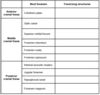

Common Medications Associated with Constipation